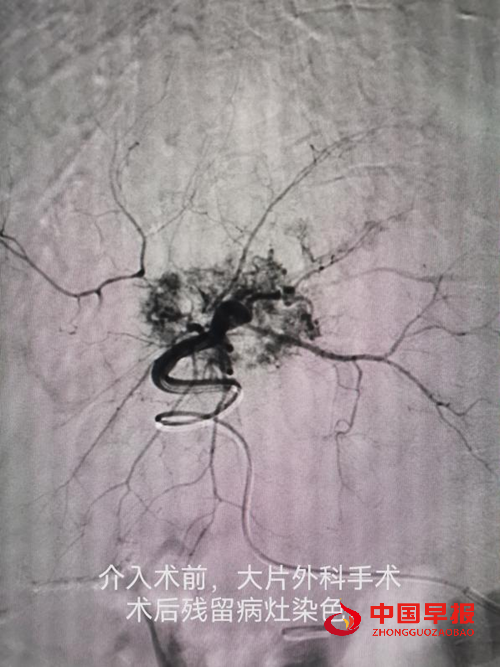

车能雨教授病例展示:

图片1.png

病例一:刘先生,男,55岁,患肺癌,经过三次介入微创手术+三次细胞治疗+靶向治疗,肺癌缩小90%,全身脊柱转移灶得到控制硬化,全身剧痛消失,处于NED状态。